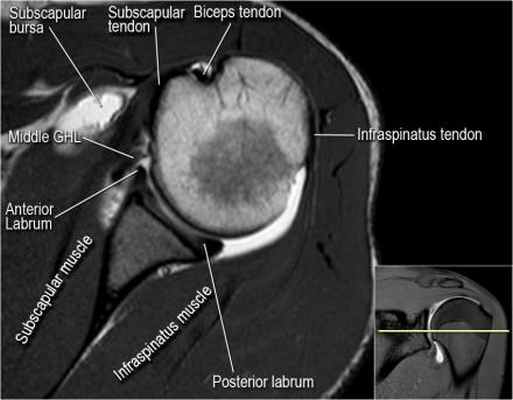

Изображение задних отделов плечевого сустава.

Отображены надостная, подостная и малая круглая мышцы и их сухожилия. Все они прикрепляются к большому бугорку плечевой кости. Сухожилия и мышцы манжеты вращателей участвуют в стабилизации плечевого сустава во время движения. Без манжеты вращателей головка плечевой кости частично сместилась бы из суставной впадины, уменьшив силу отведения дельтовидной мышцы (мышцы вращательной манжеты координирует усилия дельтовидной мышцы). Повреждение манжеты вращателей может привести к смещению головки плечевой кости кверху, в результате вызвая высокое стояние головки плечевой кости.

Нормальная анатомия плечевого сустава в аксиальных изображениях и контрольный список.

- вогнутость заднебокового края головки плечевой кости не следует путать с повреждением Хилл-Сакса, поскольку это нормальная форма для данного уровня. Повреждение Хилл-Сакса визуализируется только на уровне клювовидного отростка. В предних отделах мы сейчас на урвоне 3-6 часов. Здесь визуализируются повреждение Банкарта и его варианты.

- обратите внимание на волокна нижней плече-лопаточной связки. На данном уровне так же ищется повреждение Банкарта.